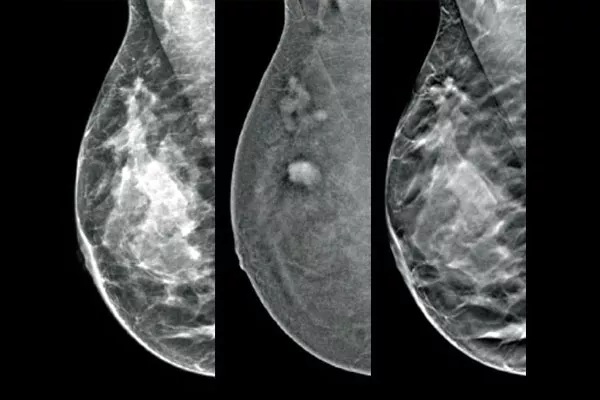

Selecione as lesões alvo identificadas na biopsia através de mamografia 2D com realce de contraste através de um procedimento por estereotaxia, com um desempenho de diagnóstico comparável ao procedimento de RM de mama.1,2 Compare as imagens pós-marcador na mesma modalidade que o exame de diagnóstico com contraste inicial.

O software de biopsia com contraste Affirm permite-lhe fazer uma biopsia às lesões identificadas durante a mamografia 2D com realce de contraste I-View™. Tirando partido do facto de fornecer imagens 2D com contraste e de tomossíntese com uma única compressão,4 o sistema de orientação para biopsia mamária vertical Affirm permite uma transição rápida do rastreio para a biopsia, tirando partido da mesma cadeia do sistema de imagem comprovado5 que o sistema de mamografia para melhorar a visualização 3D™ de lesões suspeitas.**

O sistema de imagem funcional, utilizando a CEM, assemelha-se à RM de mama, pois tem uma sensibilidade semelhante, uma especificidade mais elevada e um valor preditivo positivo mais elevado.7,8 Além disso, a CEM constitui uma alternativa de sistema de imagem de diagnóstico rentável9 comparativamente à RM, tendo um tempo de procedimento mais reduzido.7,10